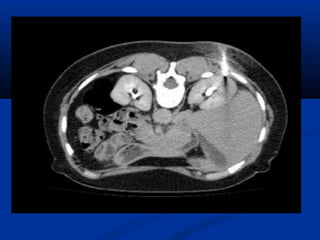

Lao niLao niệuệu

 Phân loại Elke :Phân loại Elke :

 Stade I : lao thận, X quang bình thườngStade I : lao thận, X quang bình thường

 Stade II : lao tạo hang (phá hủy < 1/3 thận)Stade II : lao tạo hang (phá hủy < 1/3 thận)

 Stade III : thận mủ > 1/3 thận (néphrectomie)Stade III : thận mủ > 1/3 thận (néphrectomie)

 UIV : khám nghiệm lựa chọn (vôi hoá, chít hẹp,UIV : khám nghiệm lựa chọn (vôi hoá, chít hẹp,

hình cộng..)hình cộng..)

Lao thaänLao thaän

Sieâu aâm:Sieâu aâm:

• **Thaän vaø nieäu quaûn:Thaän vaø nieäu quaûn:

• - Voâi hoaù trong thaän- Voâi hoaù trong thaän

• - Chít heïp = giaõn heä beå- Chít heïp = giaõn heä beå

ñaøiñaøi

• - Hình aûnh coäng: taïo- Hình aûnh coäng: taïo

hang, xoang tuûy…hang, xoang tuûy…

• - Thaän teo nhoû, voâi- Thaän teo nhoû, voâi

hoaùhoaù

• ** Baøng quang :Baøng quang : daøydaøy

vaùchvaùch

Öu theá UIV trong lao nieäuÖu theá UIV trong lao nieäu

SA giuùp ích höôùng daãnSA giuùp ích höôùng daãn